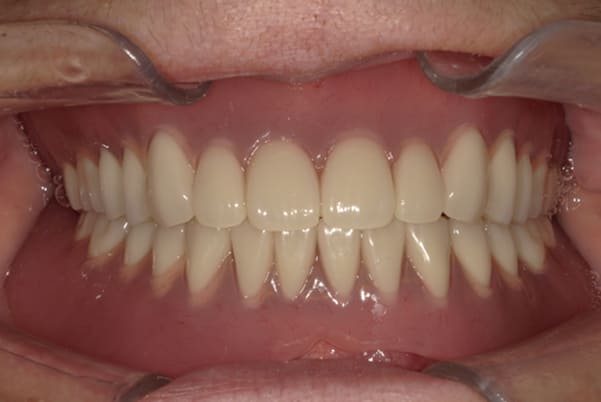

治療用入れ歯は患者様とご相談し、早急にお痛みをとり、お食事ができることをご希望されていたため、歯を抜くと同時に仮の入れ歯が入りお食事をされた後のお写真です。直ちに、お痛みを取り除き、お食事ができるような治療計画としました。

精密義歯は、歯をぬいたあと歯肉が治ってから、精密な入れ歯を作製しました。治療中も、仮の入れ歯があるため、普段の生活に支障がなく、また仮の入れ歯を実際使ってのご意見、ご希望(バネが気になる)をお聞きした上で、精密な義歯に、ご希望を反映し作製しました。

従来の方法では、歯を抜いてから入れ歯を作るまでは、歯茎の治りを待つため数か月かかりますが、患者様のご希望で、見た目、食べることに支障が出ないよう、抜歯と同時に入れ歯を装着し、歯がない期間がない入れ歯を作製したため、その日から、お食事や外出が可能となりました。

治療用入れ歯

-

精密義歯